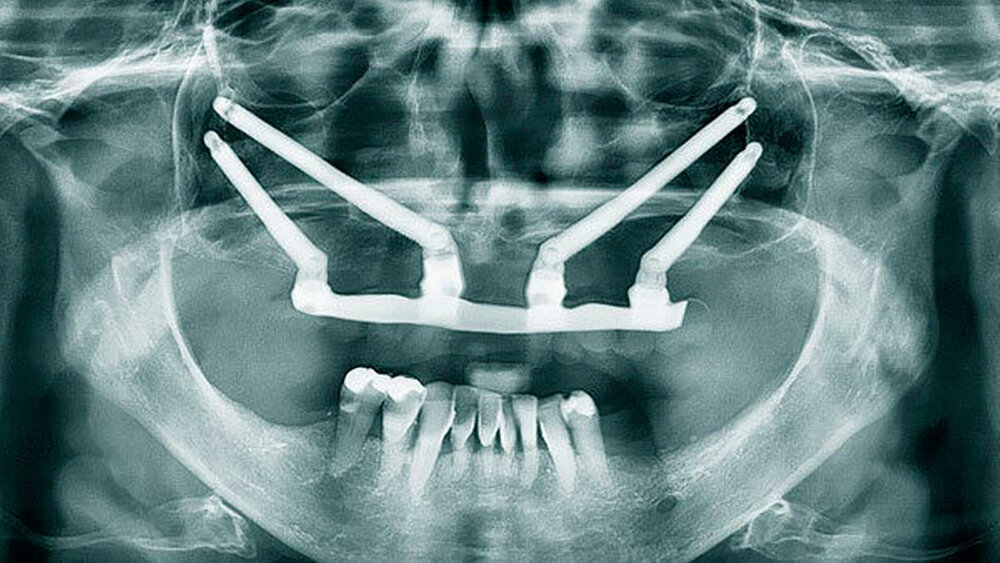

Das All-on-4 Konzept auf Zygoma-Implantaten

Eine erhebliche Erweiterung der Indikation des All-on-4 Konzeptes konnte durch den Einsatz von Zygoma-Implantaten erzielt werden. Zygoma-Implantate werden im Os zygomaticum verankert und erreichen auch in Situationen mit starker Kieferkammatrophie eine hohe Primärstabilität. Herkömmliche augmentative Verfahren können so vermieden werden. Zygoma-Implantate wurden zunächst bei Patienten mit besonderen Dysplasien im Kieferbereich und bei Tumorpatienten nach Resektion von Kieferanteilen eingesetzt. Balshi war einer der ersten Kliniker, der mit speziell gestalteten Implantaten entsprechende Fälle versorgte. Die Übertragung des All-on-4 Konzeptes auf Zygoma-Implantat-getragene Versorgungen ist insbesondere mit dem Namen Malavez verbunden, die sich sehr um diese Technik verdient gemacht hat. Dieses Konzept auf Zygoma-Implantaten wird angewendet in Fällen mit ausgeprägter Kieferkammatrophie im Oberkiefer (Abbildung 4a). Die Zygoma-Implantate werden in aller Regel in ITN inseriert. Lediglich ein externer Sinuslift ist als augmentative Maßnahme notwendig (Abbildungen 4b und c). Durch dieses Vorgehen können aufwändige augmentative Verfahren umgangen werden. Die prothetische Versorgung der Zygoma-Implantate entspricht dem Vorgehen wie beim All-on-4 Konzept und erfolgt einen Tag postoperativ. Erreicht wird, wie beim ursprünglichen All-on-4 Konzept, eine festsitzende Sofortversorgung (Abbildungen 3 und 4d).

Während die Behandlungszeit bei komplexen Augmentationen ein Jahr und mehr betragen kann, ist bei Verwendung von Zygoma-Implantaten eine festsitzende Sofortversorgung möglich. Eine Kombination von konventionellen Implantaten bei lokal ausreichendem Knochenangebot mit Zygoma-Implantaten bei lokal unzureichendem Knochenangebot ist möglich.